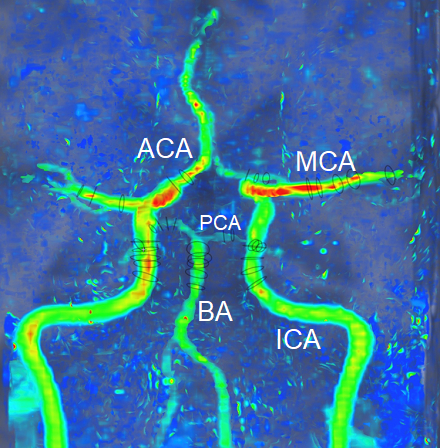

Methods We acquired both 4D flow brain MRI and 4D flow cardiac MRI in a single session using a Siemens 3T Magnetom Vida scanner in 5 volunteers (4 male, 1 female) 31.2 ± 10.4 years old. Using a compressed sensing protocol (R=7.7) each 4D flow scan was acquired in under 15 minutes. Brain and cardiac MRI respectively used a 1.4 mm3 and 2.1 mm3 voxel size; velocity was encoded in 3D at 120 cm/s and 200 cm/s, with 15-25 cardiac phases. 4D flow brain coverage included the ICA, BA, MCA, ACA, and PCA (Fig 1). 4D flow cardiac coverage included the ascending and descending thoracic aorta (Fig 2). 4D flow data were reconstructed using Tempus Pixel (Tempus, IL) and regions of interest were defined to measure volumetric flow rate (Q). Blood flow pulsatility over the cardiac cycle was quantified using pulsatility index (PI). Pearson’s correlation coefficient (r) was calculated for statistical analysis.